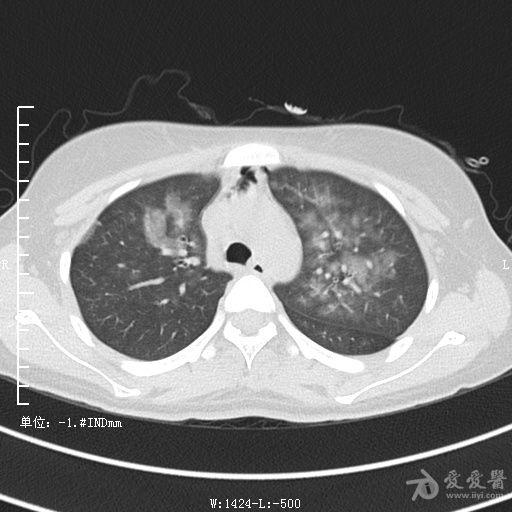

典型支气管扩张及肺水肿CT片

典型支气管扩张肺水肿